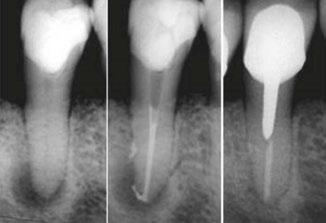

Figures 1-3: Clinical case performed by Dr. Benedict Bachstein

Clinical case performed by Dr. Benedict Bachstein (Figures 1-3)

The patient was diagnosed with irreversible pulpitis in tooth number 14, which presented multiple canals with highly complex anatomies. All canals were instrumented to 25/.04 and cleaned with Odne®Clean following the recommended clinical protocol. The use of Odne®Clean enabled the identification of five canal orifices and clearing of apical deltas.

Clinical case performed by Dr. Brett Gilbert (Figures 4 and 5)

In this case, Dr. Gilbert was initially unable to locate the MB2 canal, despite thorough attempts using ultrasonic and a microscope. After performing the irrigation protocol with Odne®Clean, the MB2 became visible. Following activation, the filling material extended completely through the MB2.